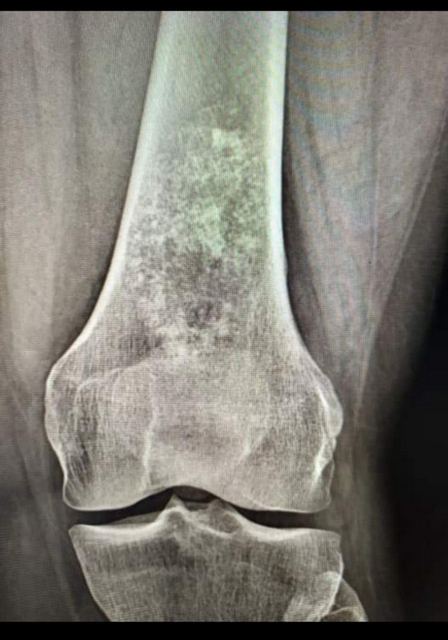

Уже більше, ніж пів року, розповідає Олеся Кондратюк, вона страждає на біль у суглобі та кульгавість. Спершу вона не звертала на це уваги. А в січні жінка впала на коліно та дуже забилася. Тоді ж біль посилився, й оперативно довелося зробити рентген. Як наслідок, побачили пухлину. Уже після біопсії в Києві та Харкові виявилося, що вона злоякісна. Жінку направили в Інститут патології хребта та суглобів ім. професора М. Г. Ситенка НАМН «України» (м. Харків), де вона нині й перебуває.

Нижче – фотопідтвердження діагнозу співробітниці «Нової якості», рентген- і КТ-знімки пухлини.